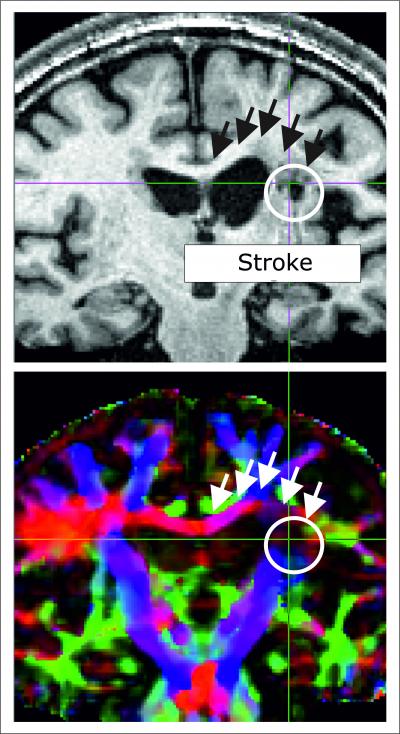

The structure of the corpus callosum, a thick band of nerve fibres that connects the two halves of the brain with each other and in this way enables the rapid exchange of information between the left and right hemispheres, plays an important role in the regaining of motor skills following a stroke. A study currently published in the journal Human Brain Mapping has shown that in stroke patients with particularly severely impaired hand movement, this communication channel between the two brain hemispheres in particular was badly damaged.

In order to demonstrate the structural connection between brain areas, the Cologne researchers used diffusion-based magnetic resonance imaging (dMRI), which can be used to reconstruct longer stretches of nerve fibres. dMRI is based on the principle that cell elements, such as the membrane or extensions, inhibit the spread of water molecules thereby preventing them from diffusing randomly in all directions. Consequently, parallel nerve fibres can be clearly identified using dMRI. Compared to the healthy control group, the stroke patients had lower diffusion values in the corpus callosum region. This would indicate that this interhemispheric communications connection was damaged by the stroke. The most significant deviations from the values of the control group were observed in patients with more severe motor defects and increased activity in the healthy brain hemisphere.